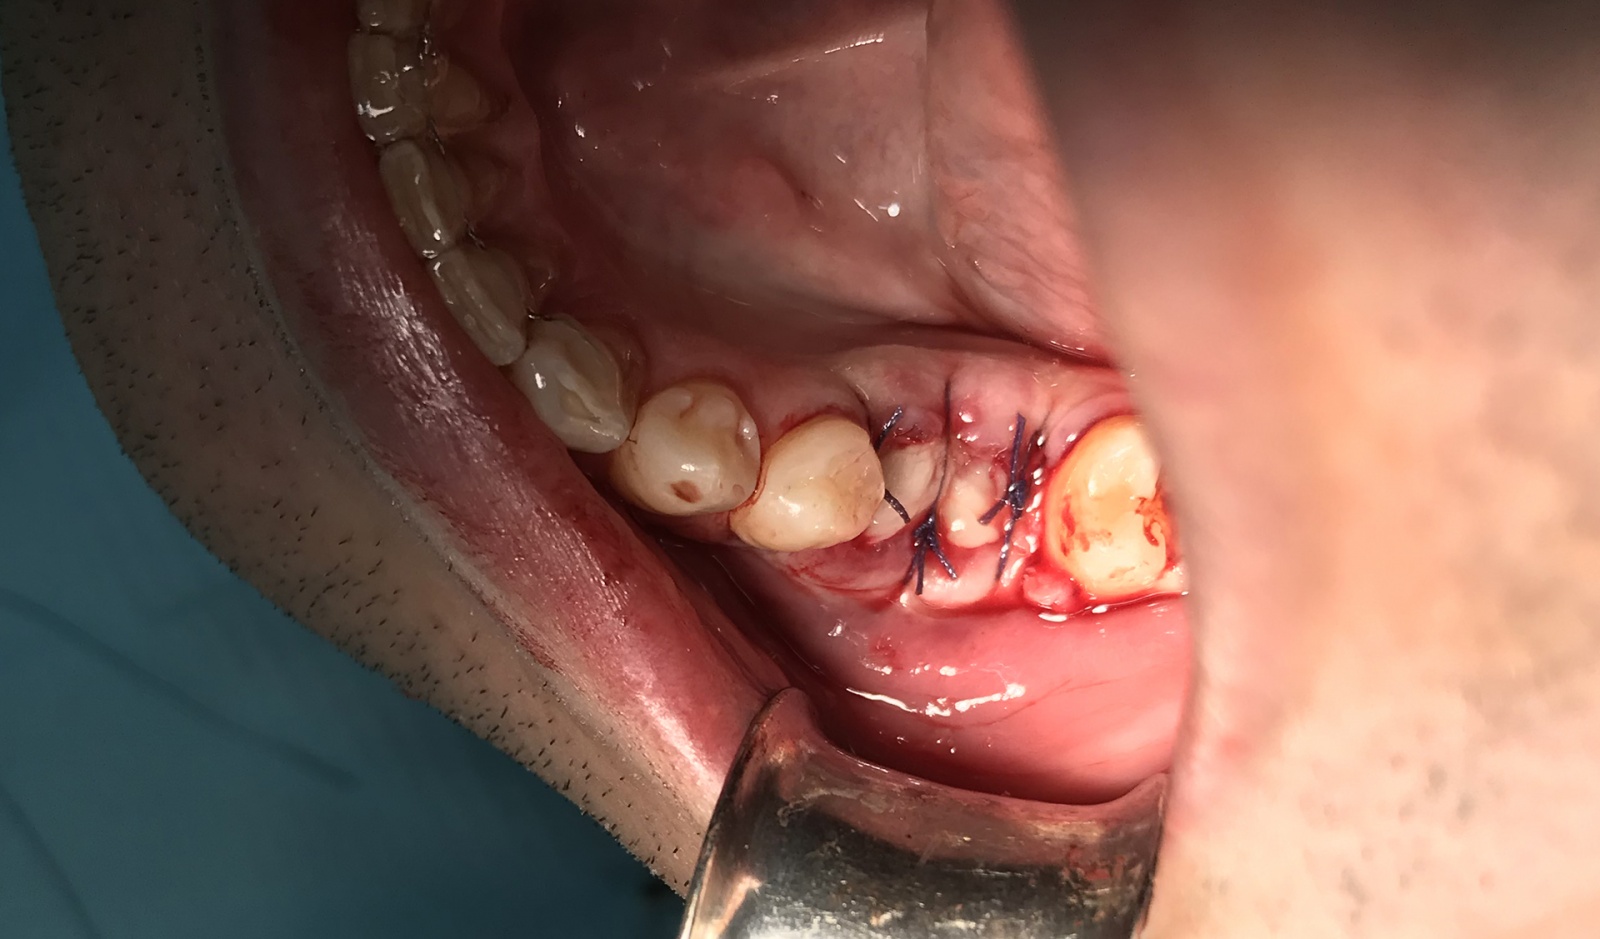

4.8. Финальные этапы восстановления челюстной кости.

После заполнения костной массой, сверху все дело покрыли фибрином, а поверх фибрина, сверху все дело закрыли коллагеновой мембраной. Дело в том, что если этого не сделать, костная масса будет постоянно смещаться, процесс заживления усложняется, масса хуже прорастает кровеносными сосудами, а так же значительно повышается вероятность инфекций.

В моем случае был использован второй вариант — изготовление мембраны из моей плазмы.

Фотография после установленной мембраны

В конце, все это дело было сшито несколькими швами.